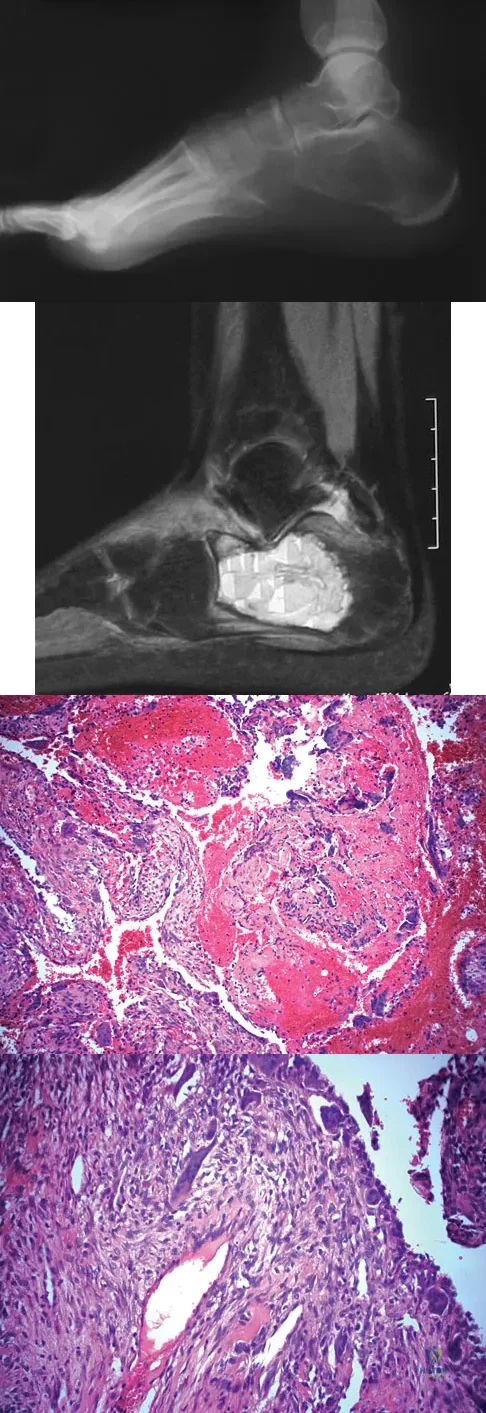

Question 19:

A 16-year-old girl injured her hip in a fall. Radiographs are shown in Figures 14a and 14b. She denies any history of pain prior to the fall and is currently asymptomatic. A bone scan, MRI scan, and biopsy specimens are shown in Figures 14c through 14f. What is the most likely diagnosis?

Options:

- Osteosarcoma

- Fibrous dysplasia

- Osteoblastoma

- Ossifying fibroma

- Osteomyelitis

Correct Answer: Fibrous dysplasia

Explanation:

Although the classic radiographic appearance of fibrous dysplasia is one of a central metaphyseal lesion with ground glass matrix, it is not unusual to see either a more radiodense-appearing lesion or a more peripheral location. The histologic finding of spicules of woven bone without osteoblastic rimming in a bland fibrous background is diagnostic of fibrous dysplasia. The imaging studies could be consistent with low-grade osteosarcoma, osteoblastoma, or osteomyelitis, but all have a very different histologic picture. Observation is indicated in the absence of symptoms, impending fracture, or deformity. Fibrous dysplasia most commonly occurs in the proximal femur. Huvos AG: Bone Tumors: Diagnosis, Treatment, and Prognosis. Philadelphia, PA, WB Saunders, 1991, pp 30-43.

References:

DiCaprio MR, Enneking WF: Fibrous dysplasia: Pathophysiology, evaluation, and treatment. J Bone Joint Surg Am 2005;87:1848-1864.